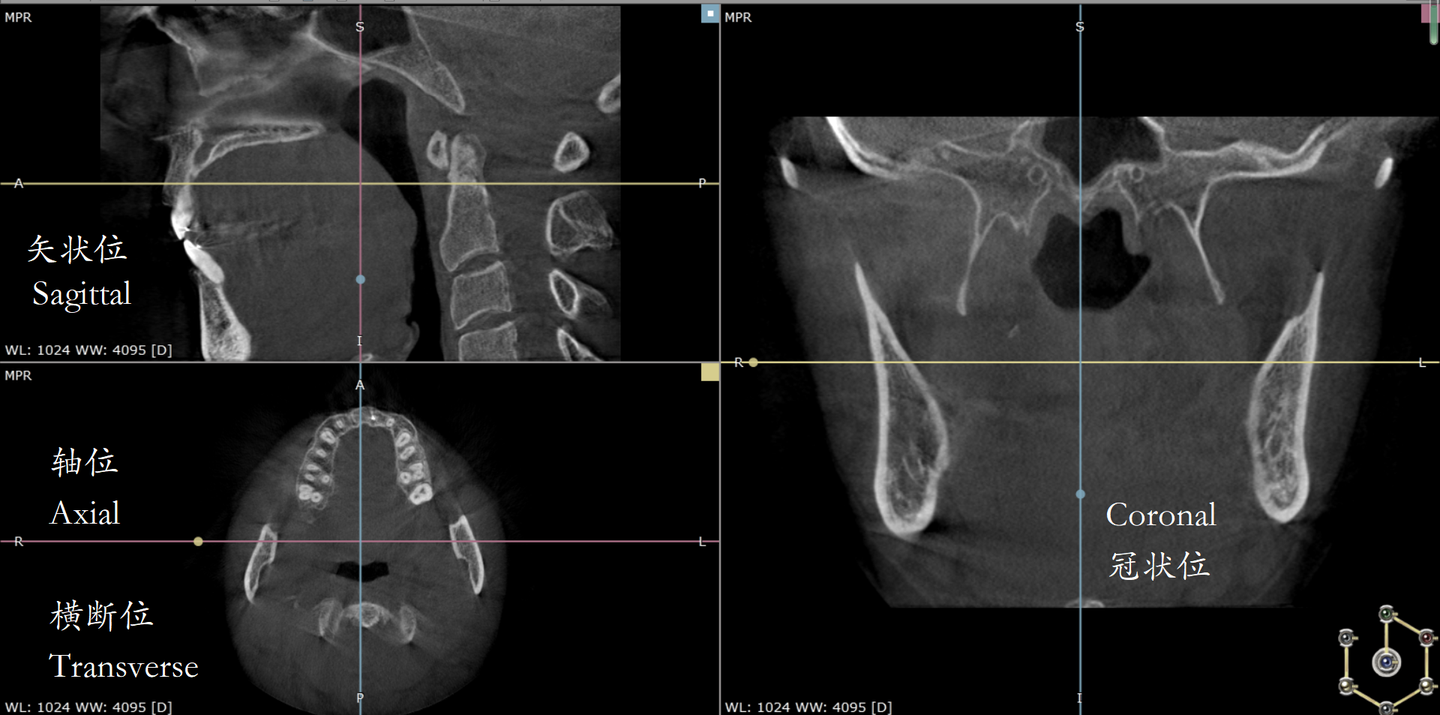

矢状面、冠状面、横断面的定义

人体结构∩矢状面=矢状位

人体结构∩冠状面=冠状位

人体结构∩横断面=横断位